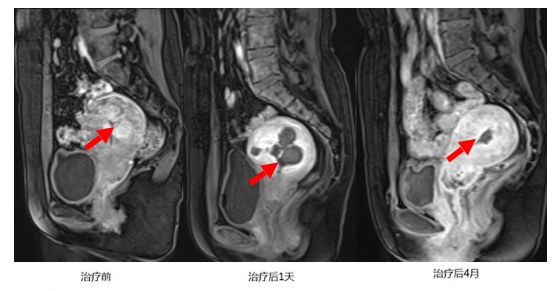

术后效果如何评价

我们在治疗过程当中应用超声造影进行实时的效果评价,病灶坏死后会出现很明显的灰度改变;此外,我们应用术前术后增强磁共振对比来进行疗效评价;通过对治疗后的患者的随访,我们发现超声消融治疗效果不管是症状缓解还是术后肌瘤再次复发,效果都是与开腹和腹腔镜治疗相当的,甚至优于传统手术治疗。术前术后效果对比图如下